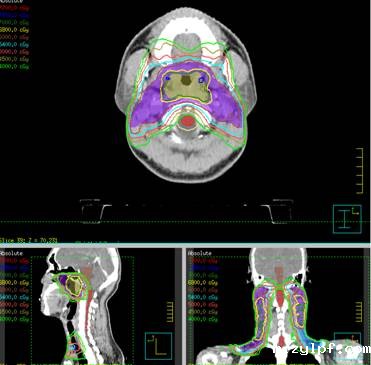

我科常见病种的靶区计划图:

鼻咽癌调强放疗IMRT